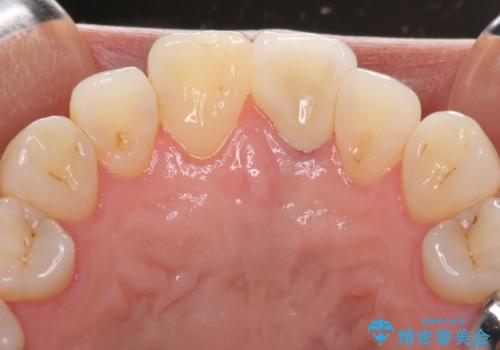

変色とともに、捻れていたことも気になっていたので、その両方を解決させることとしました。

オーダーメイドタイプのクラウンを選択いただいたので、まるで天然の歯と見間違うほど自然に仕上がり、患者様には大変満足していただきました。